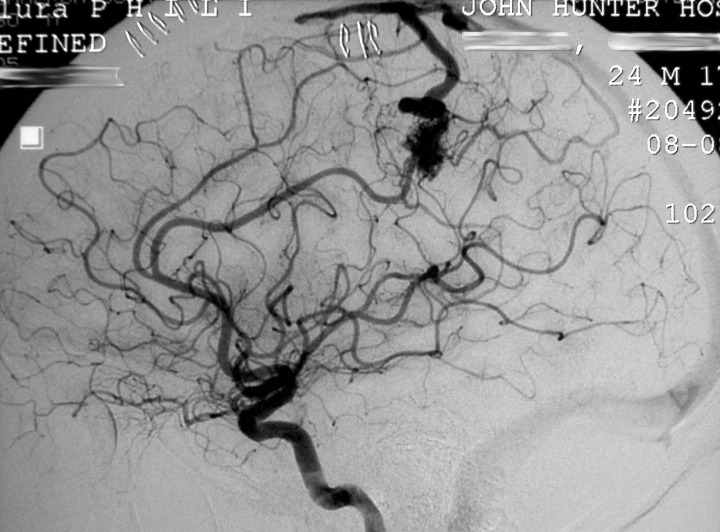

Визуализация и особенности капиллярно-венозной мальформации